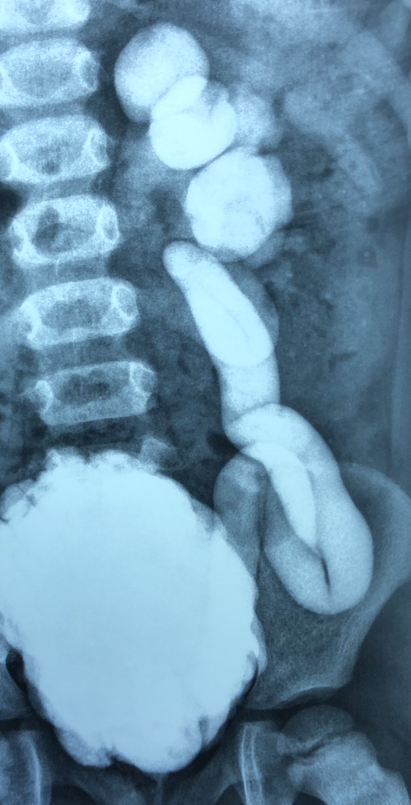

To control uremia with fluid retention, intermittent HD was initiated. Abdominal U/S and MRI demonstrated severe bilateral hydroureteronephrosis and no stricture of distal urethra. The spine and spinal cord were normal as seen on MRI. Ampicillin and ceftriaxone were administered for 2 weeks; BUN and creatinine decreased to 19 and 1.2 mg/dl, respectively, on the 7th hospital day, and HD was withdrawn. VCUG revealed chronic non-anatomical bladder outlet obstruction and severe bilateral reflux (right, grade 4–5; left, grade 5) with hydroureteronephrosis. Clean intermittent catheterization (CIC) four times a day was performed; however, on the 20th hospital day, she developed repeated UTI and was transferred to our hospital.

Diagnostic test was done